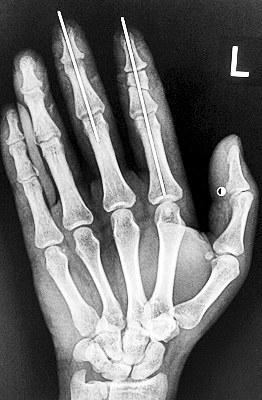

術(shù)后X光顯示,骨骼對位良好。

最終,盧微波和團(tuán)隊(duì)找好了需要的血管和神經(jīng),做好標(biāo)記后,開始固定食指骨骼、吻合肌腱,最后在顯微鏡下用直徑20微米的無創(chuàng)顯微縫合線開始吻合血管和神經(jīng)。

在經(jīng)過兩個多小時手術(shù)后,早上8時許,盧微波下令松止血帶,數(shù)十秒后男子蒼白的食指逐漸紅潤起來,食指在離體10個小時后恢復(fù)血運(yùn)。

緊接著,盧微波又開始中指再植手術(shù)。上午10時許,中指在離體12小時后也成功恢復(fù)血運(yùn)。